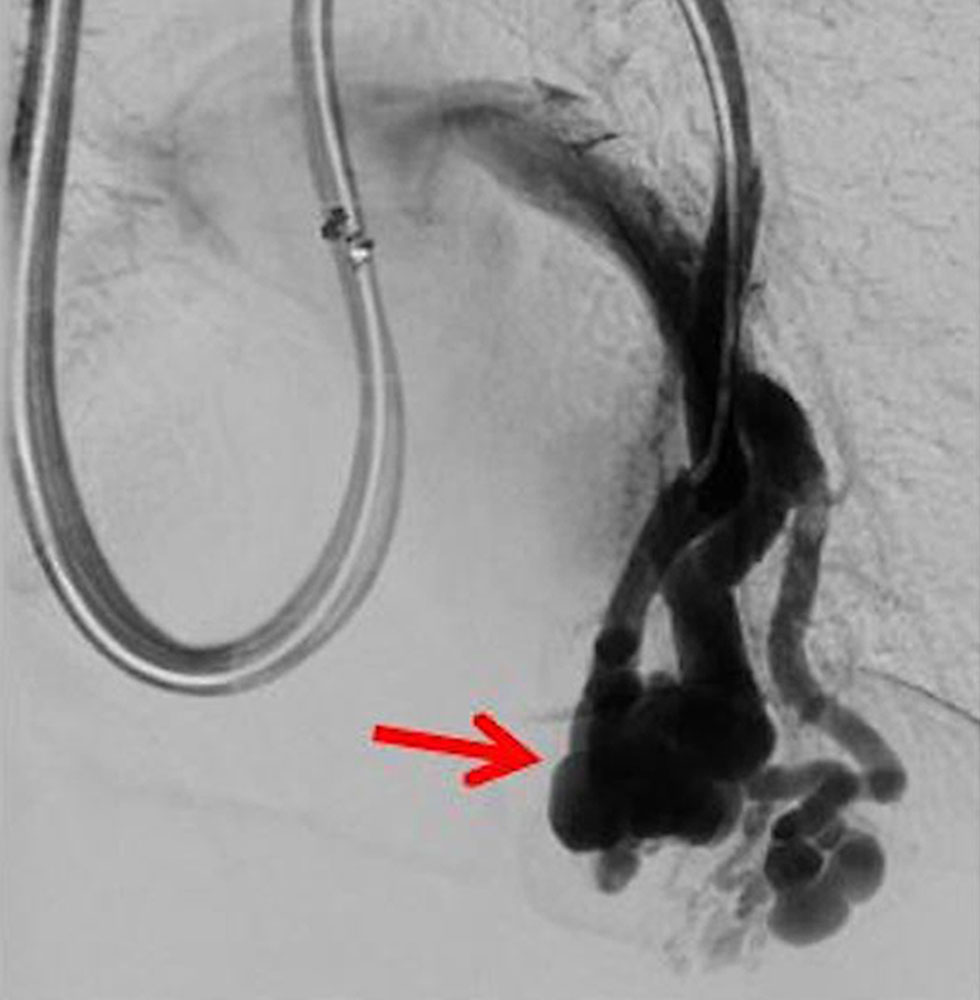

Bei einigen Patientinnen mit bisher unbehandelten oder nicht suffizient behandelten venösen Malformationen, bei denen eine Verbindung ins tiefe Leitvenensystem vorliegt („Kommunikationsvene“ oder Marginalvene) mit entsprechend erhöhter Gefahr einer Thrombose oder Thrombembolie, kann die Gefahr dieser Komplikation während der Schwangerschaft erhöht sein. Eine entsprechende Therapie vor der Schwangerschaft mit interventionellem oder operativem Verschluss dieser Kommunikationsvenen kann dieses Risiko erheblich vermindern oder ausschließen. Bei einzelnen Patientinnen kann zudem in Abwägung des individuellen Risiko-Nutzen-Verhältnisses während der Schwangerschaft eine längerdauernde Antikoagulation mit Heparin sinnvoll und notwendig sein. Daten liegen hier vor bei Patientinnen mit Klippel-Trénaunay-Syndrom (KTS), die allerdings keine ganz einheitlichen Ergebnisse zeigten. Einerseits bestand kein Unterschied in der Komplikationshäufigkeit zwischen schwangeren und nicht schwangeren Frauen mit Klippel-Trénaunay-Syndrom, dennoch war das Komplikationsrisiko im Vergleich zu Normalschwangeren erhöht, auch trat eine doppelt so hohe Rate an postpartalen Blutungen auf. In einer weiteren Studie, die KTS-Patientinnen mit nicht erkrankten Schwangeren verglich berichteten 43 % der KTS-Patientinnen über mehr Symptome während Schwangerschaft.

Bei Patientinnen mit arteriovenösen Malformationen, vor allem aber auch bei Patientinnen mit HHT-Morbus Osler und arteriovenösen Malformationen der Lunge oder der Leber, ist vorher oder bei Eintritt einer Schwangerschaft ein genauer Status der Veränderungen zu erheben, insbesondere sind aneurysmatische Erweiterungen der Blutgefäße (Aneurysmen) auszuschließen bzw. zu vermessen. Es kommt hier manchmal zu einer schnellen, erheblichen Erweiterung dieser Aneurysmen, die zu gefährlichen Blutungen führen können. Aus der Literatur ist bekannt, dass es besonders im 2. und 3. Trimenon hier zu Verschlechterungen kommen kann mit vermehrten Blutungen bei arteriovenösen Malformationen der Lunge und Leber (high-output cardiac failure), auch paradoxe Embolien wurden beschrieben.